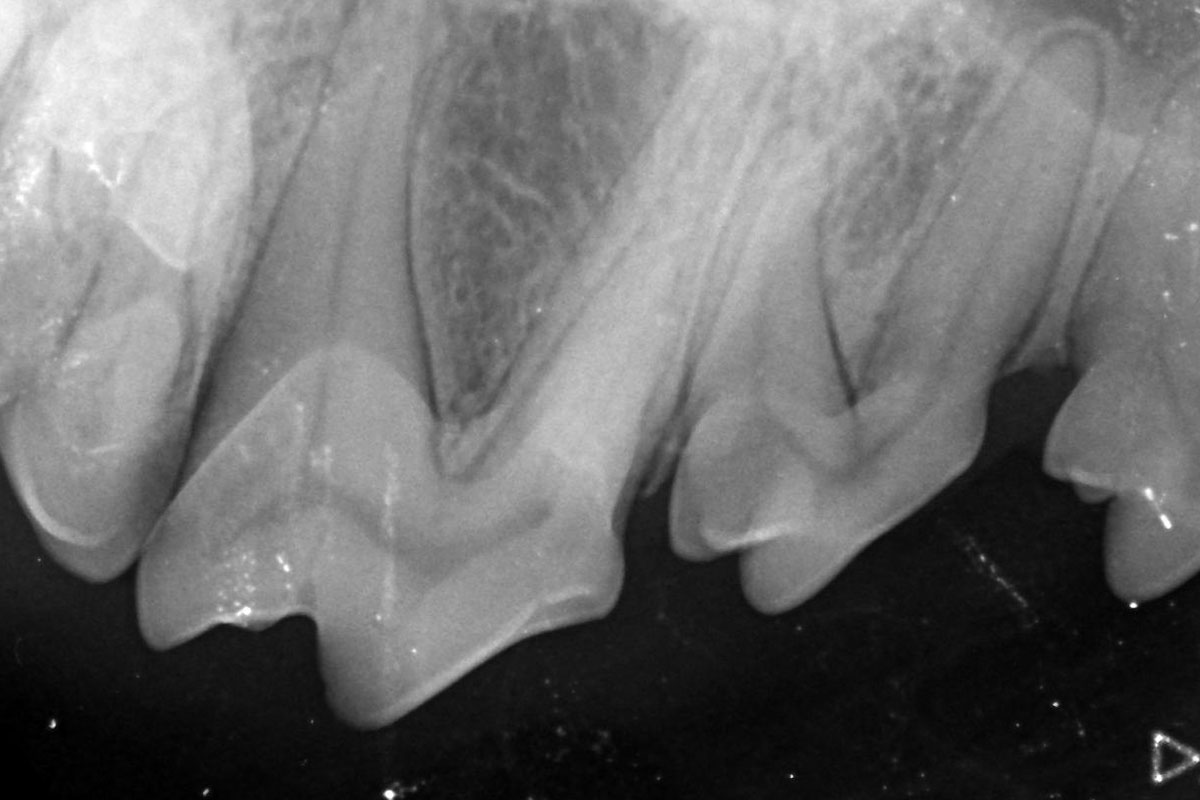

Bei einer Zahnuntersuchung ohne Röntgenbild können nur die Zahnkronen und das Zahnfleisch beurteilt werden, alles darunter bleibt verborgen. Erst mithilfe des Dentalröntgens können auch schmerzhafte pathologische Prozesse der Zahnwurzeln erkannt und behandelt werden. Durch die Röntgenaufnahme direkt in der Maulhöhle kommt es zu keinen Überlagerungen, Zähne und Wurzeln sind besser sichtbar. Das ist speziell bei Katzen wegen der Möglichkeit einer schmerzhaften Zahnresorption wichtig, aber auch bei anderen Tierarten ist intraorales Röntgen von großem Vorteil.